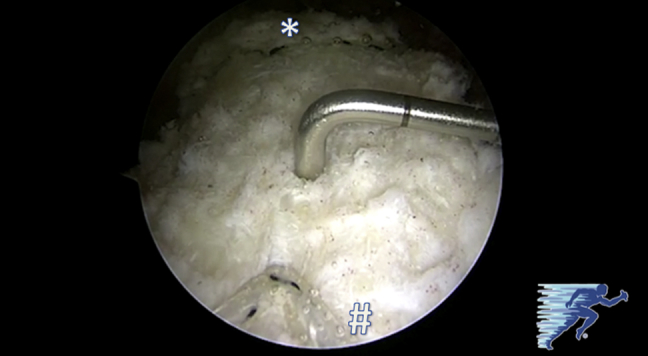

Once the massive irreparable posterosuperior rotator cuff tear is confirmed, the size of the tear is measured in the sagittal and coronal planes with an arthroscopic ruler (Arthroscopic Measurement Probe, 220 mm, 60°; Arthrex) to determine the size of the patch that will be used to reconstruct the superior capsule (Fig 1). This should be performed after extensive debridement of the remaining cuff tissue back to stable margins.

Fig 1.

The size of the tear at the greater tuberosity is measured with an arthroscopic ruler (Arthroscopic Measurement Probe, 220 mm, 60°) through the anterolateral portal to determine the size of the patch that will be used to reconstruct the superior capsule (left shoulder, with arthroscopic visualization from posterolateral portal). The asterisk indicates the glenoid, and the pound sign indicates the humeral head.